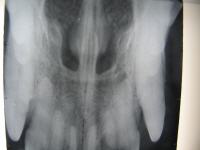

Röntgenuntersuchung:

Vor der Operation wurde ein Röntgenbild mit einem speziellen Zahnröntgengerät erstellt, damit das ganze Ausmaß der Tumorwucherung ersichtlich wurde. Auf dem Röntgenbild ist sehr deutlich zu sehen, dass bereits der Knochen betroffen war.